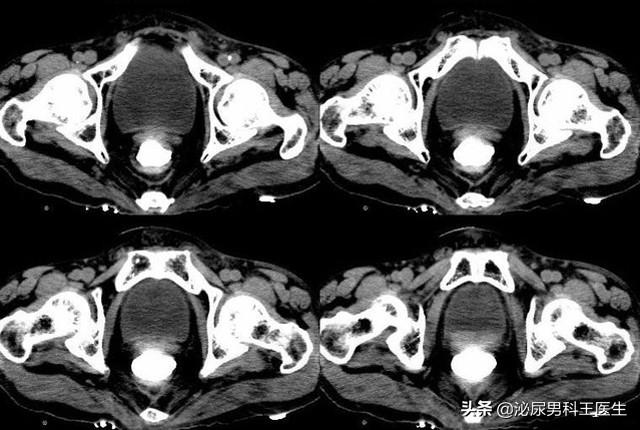

结果在一系列检查后被确诊了III期直肠癌,由于肿瘤目前已经很大且离肛门比较近,想要活命只能是连同肛门一起切除。

比如膀胱癌会根据情况切除患者膀胱,而如果是直肠癌就会切除患者的直肠和肛管,并在患者的腹部开一个小口,将肠管转移到体表而形成的人造切口。

人造切口后可以减轻患者的肠梗阻,保护远端的管道免受损伤,促进患者泌尿系统和肠道疾病的痊愈。在生活中比较常见的包括回肠造口、尿路造口以及结肠造口等,患者可通过此口完成排尿、排便,这类人群在医学术语上就叫做“造口人”。